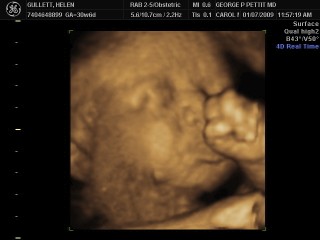

Saat pemeriksaan rutin yang kelima, saya sudah 63 kg dan bayi saya sudah berusia 31 minggu. Saat itu, di layar TV kami melihat hasil USG yang luar biasa!

Sudah dapat dipastikan bayi kami adalah perempuan. Detak jantungnya dapat direkam dan dilihat dalam diagram juga. Puji Tuhan dia adalah bayi yang sehat. Selain itu, sudah dengan jelas dapat dilihat wajah bayi kami walaupun dia masih menutup mata (malu yah…) dan mencoba menutup wajahnya dengan tangan dan kakinyanya lagi. Pertumbuhan organ tubuhnya sudah lengkap dan dapat dengan jelas dilihat. Saat mengukur sudah berapa besar ukuran bayi kami, dokter mengatakan bahwa dia lebih besar dari ukuran yang seharusnya pada usianya yang masih 31 minggu. Dokter juga mengatakan bahwa hasil pemeriksaan gula darah/diabetes saya adalah normal, jadi bayi ka mi sehat dan ukurannya yang besar karena dia memang tumbuh dengan sehat dan cukup gemuk. Hal ini menjelaskanuga masalah dengan urat saraf di pinggang. Namun, kami sangat bersyukur karena tahu bahwa semua yang berhubungan dengan bayi dan keadaan saya adalah normal dan kami berdua dalam keadaan sehat. Sungguh tangan Tuhan tetap menjaga kami berdua dan suami saya juga.